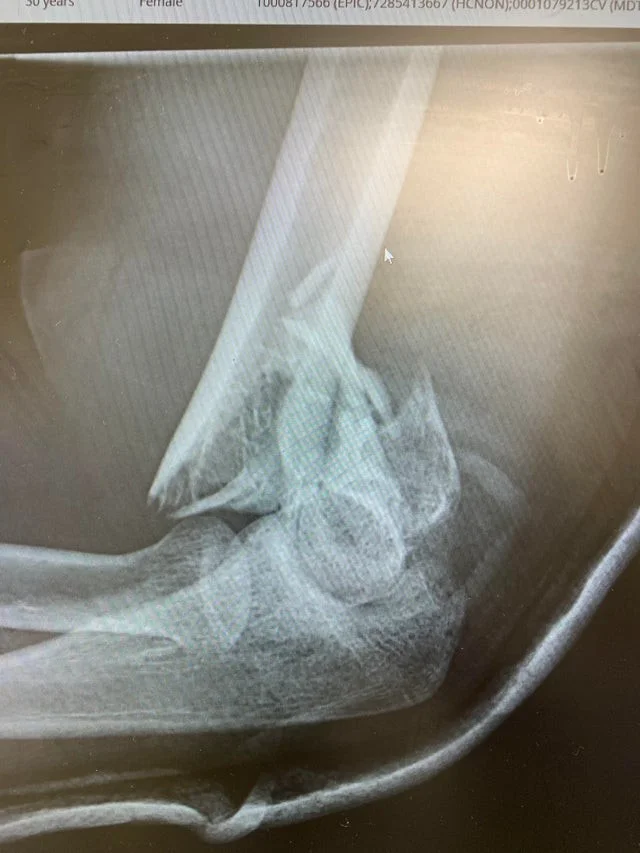

Мужчина повредил руку